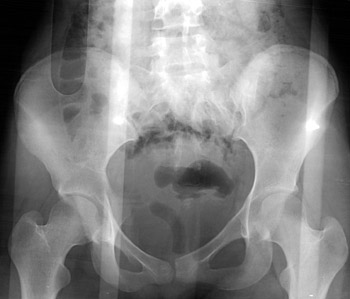

AP view of pelvis | |